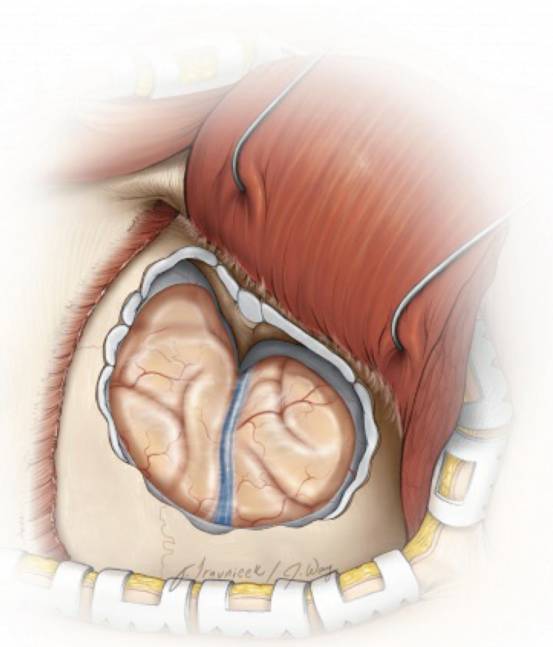

图2. 图示右侧外侧蝶骨嵴脑膜瘤及其与周围结构的关系。